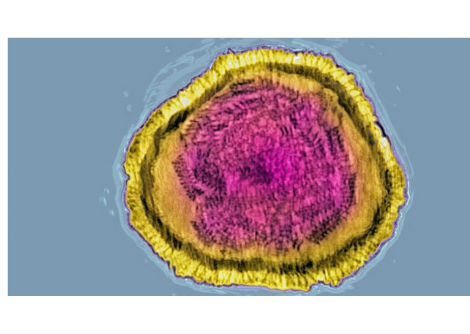

لإنشاء شاشة عرض حية، قام الباحثون بتعديل الخلايا الجذعية للبشرة وراثيًا بحيث تستجيب لإشارات الالتهاب داخل الجسم. عند تنشيط مسار رئيسي مرتبط بالالتهاب، يُعرف باسم NF-κB، تُنتج الخلايا المُهندسة بروتينًا فلوريًا أخضر.

ثم استُخدمت هذه الخلايا المُعدّلة لزراعة أنسجة جلدية، زُرعت على فئران. بعد التئام الطعوم واندماجها مع الأنسجة المحيطة، تصرفت البشرة المُهندسة بشكل مشابه للبشرة الطبيعية، باستثناء فرق جوهري واحد. فعندما يحدث التهاب داخل الجسم، تبدأ المنطقة المزروعة بالتوهج باللون الأخضر.

يُترجم هذا التوهج إشارة جزيئية غير مرئية إلى إشارة مرئية، مما يسمح بقراءة النشاط البيولوجي الداخلي مباشرةً على سطح الجلد. ولأن المستشعر مصنوع من خلايا جذعية حية، فهو لا يعتمد على الإلكترونيات أو مصادر الطاقة أو الاستبدال الدوري. ومع تجدد الجلد بشكل طبيعي، تستمر الخلايا الجذعية المُهندسة في إنتاج خلايا استشعار جديدة.